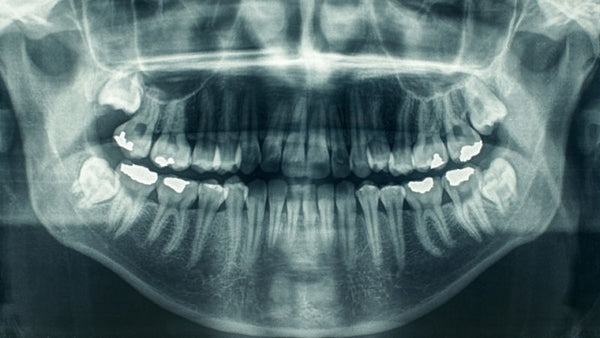

La radiographie numérique remplace la radiographie avec pellicules et L'appareil panoramique numérique vous permet de prendre des images numériques de haute qualité avec une dose de radiation diminuée.permet de conserver les images prises dans votre dossier patient informatisé.